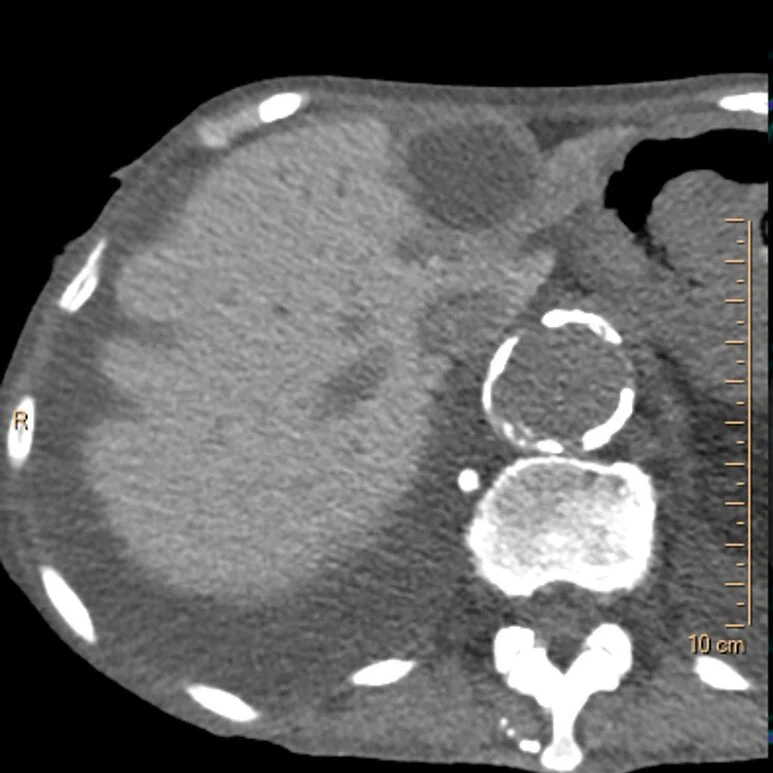

Conventional CT: Hyperdense liver. There is no contrast in the aorta.